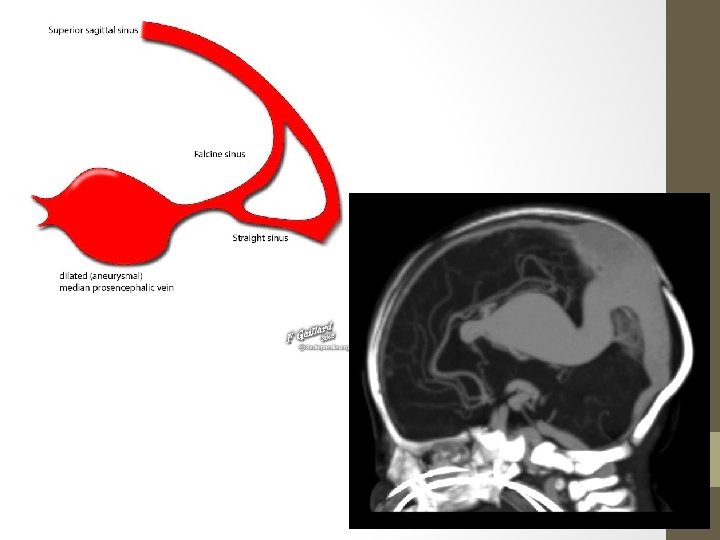

Vein Of Galen Malformation • The most frequent arteriovenous malformation in neonates. • Results from an aneurysmal malformation with an arteriovenous shunting of blood • Develops during weeks 6 -11 of fetal development as a persistent embryonic prosencephalic vein of Markowski • Typically result in high-output congestive heart failure or may present with developmental delay, hydrocephalus, and seizures. (vary with the type of malformation) • Has been associated with capillary malformationarteriovenous malformation (CM-AVM), which is a newly recognized autosomal dominant disorder, caused by mutations in the RASA 1 gene in 6 families

• Presentation commonly with high output cardiac failure in neonates while mostly hydrocephalus in infants and children • Angiography: gold std • Classification - Lasjaunias classification: Ø Choroidal: tend to present earlier (neonate) with more severe shunts&high output cardiac failure Ø Mural: present later (infant) and typically with hydrocephalus. Fewer fistulas-high outflow restriction -Yasargil Classification Ø type I: small pure cisternal fistula between the vein of Galen and either the pericallosal arteries (anterior or posterior) or posterior cerebral artery Ø type II: multiple fistulous communications between the vein of Galen and the thalamoperforating vessels Ø type III: high flow mixed type I and II Ø type IV: parenchymal arteriovenous malformation (AVM) with drainage into the vein of Galen